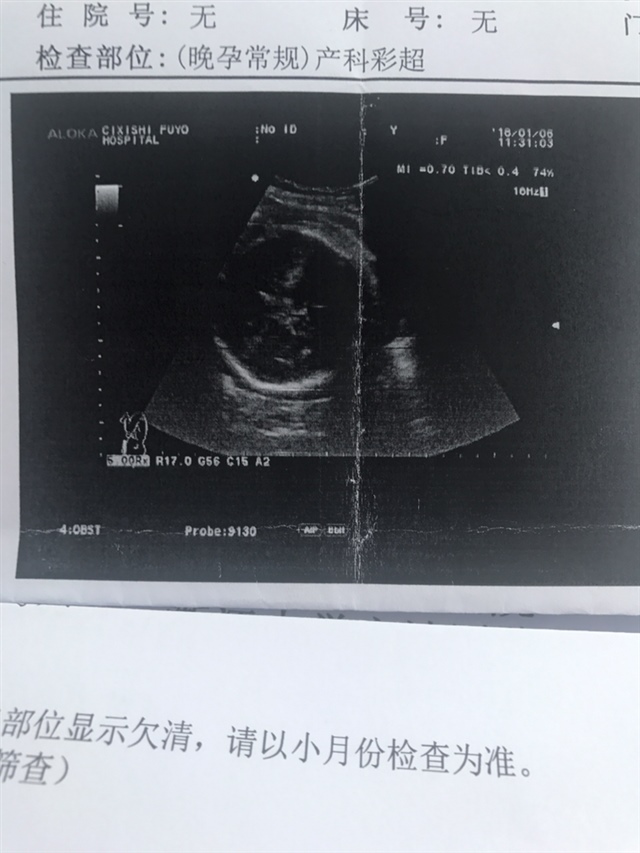

宝宝5个月16天

男孩吧